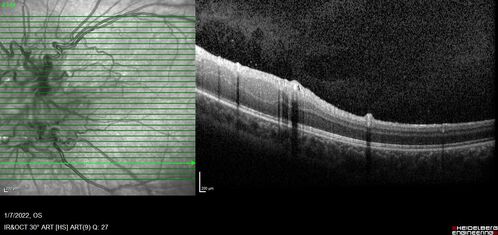

Combined hamartoma of the retina and retinal pigment epithelium

8 year old boy failed vision screening at school. VA 20/20 OD, 20/40 OS

Combined hamartoma of the retina and the retinal pigment epithelium